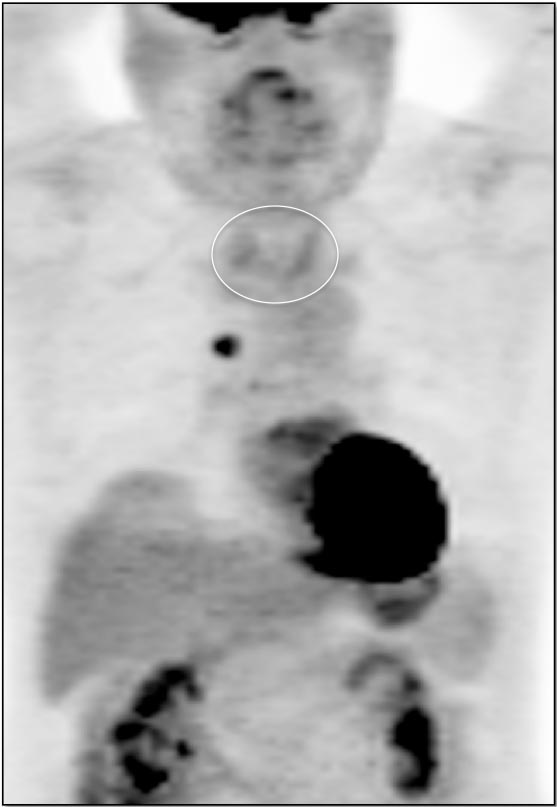

Case 4 (Image 2)

Axial images confirm the uptake to represent a hypodense left lobe thyroid nodule, containing a punctate calcification. As ≈ 30% of hypermetabolic thyroid nodules represent a primary thyroid cancer, such nodules require ultrasound evaluation (biopsy is usually necessary). In this case, biopsy revealed a primary thyroid cancer.